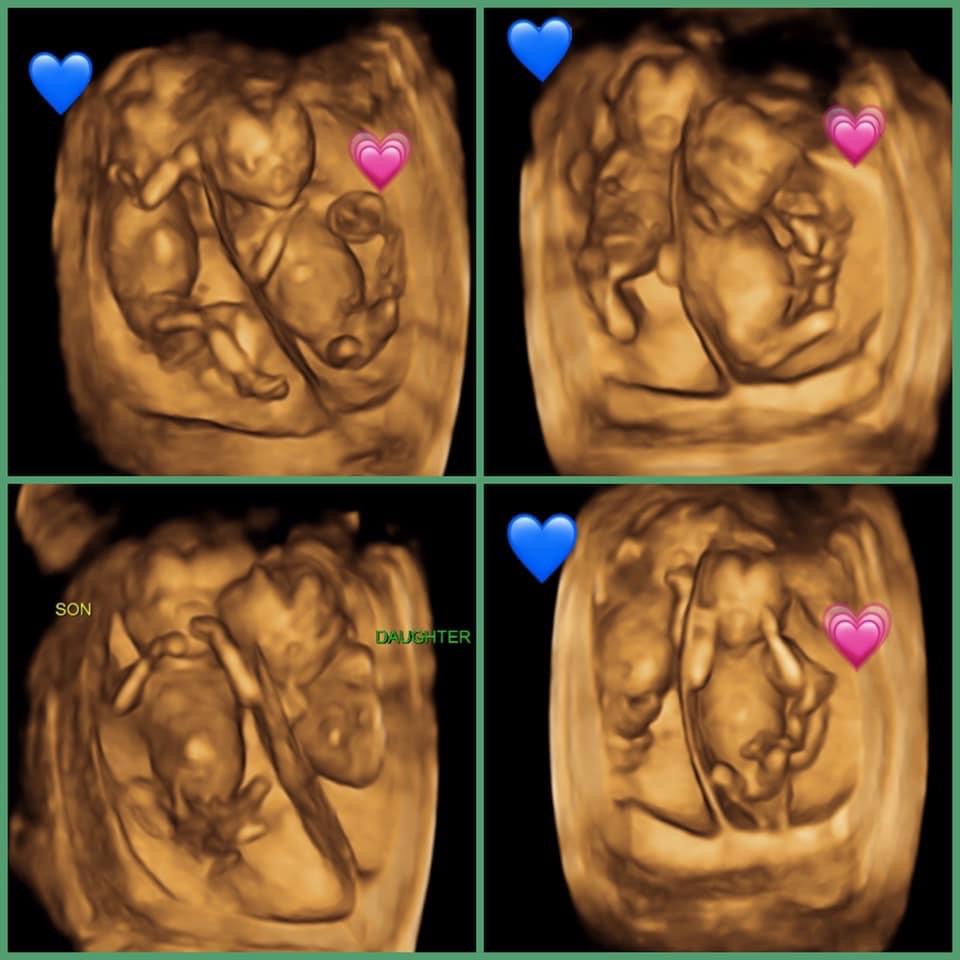

drbinh.com20 Weeks Pregnant With Twins Ultrasound

drbinh.com20 Weeks Pregnant With Twins Ultrasound